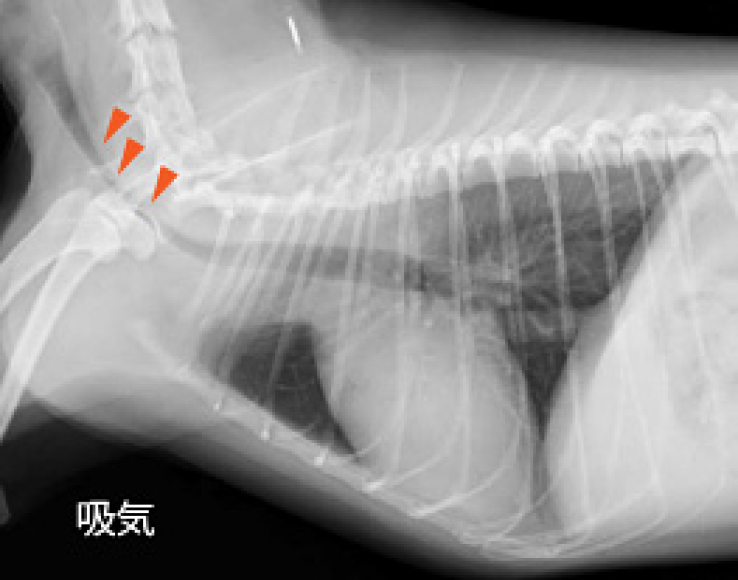

レントゲン検査によって肺や気管の状態を確認することができます。肺野の病変の画像パターンを分類し、どのような疾患が疑わしいのか診断することができます。また、吸気時と呼気時のレントゲン写真を撮ることによって、気管虚脱の有無を診断することができます。当院では、単純なレントゲン撮影では判断の難しい気管虚脱に対しても透視下のレントゲン撮影が可能であり、動的に気管虚脱を診断することができます。超音波検査は、胸水や腫瘤の診断に役立ちます。また、呼吸器症状の原因となりうる心臓疾患の存在を診断することができます。

気管虚脱

トイ犬種、小型犬、および肥満犬に多い病気です。「ガーガー」というガチョウの鳴き声の様な咳をするのが特徴です。正常な気管は軟骨によって支えられていますが、気管虚脱では軟骨の変性に伴い気管が潰れるため、呼吸困難になってしまいます。気管の潰れ方が大きいほど症状も重篤になります。気管虚脱は進行していくため、症状が軽いうちに診断し軟骨の保護を行うことや、体重を適正に管理することで進行を抑えることができると考えられています。